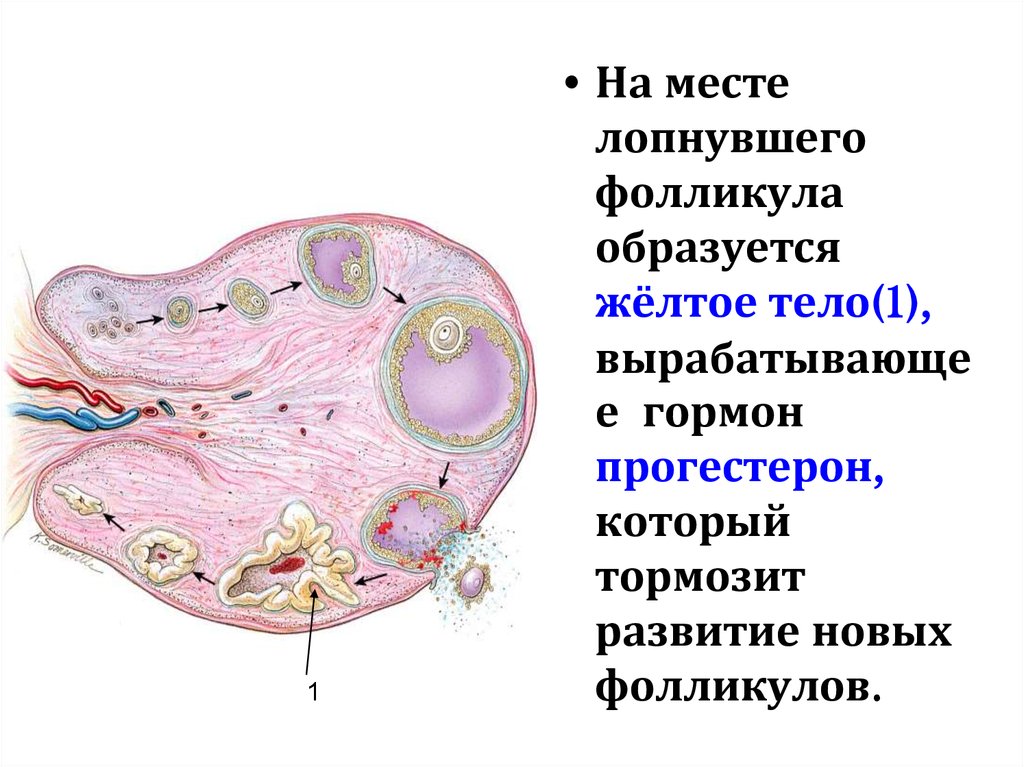

Созревание фолликула в яичнике: этапы и процессы